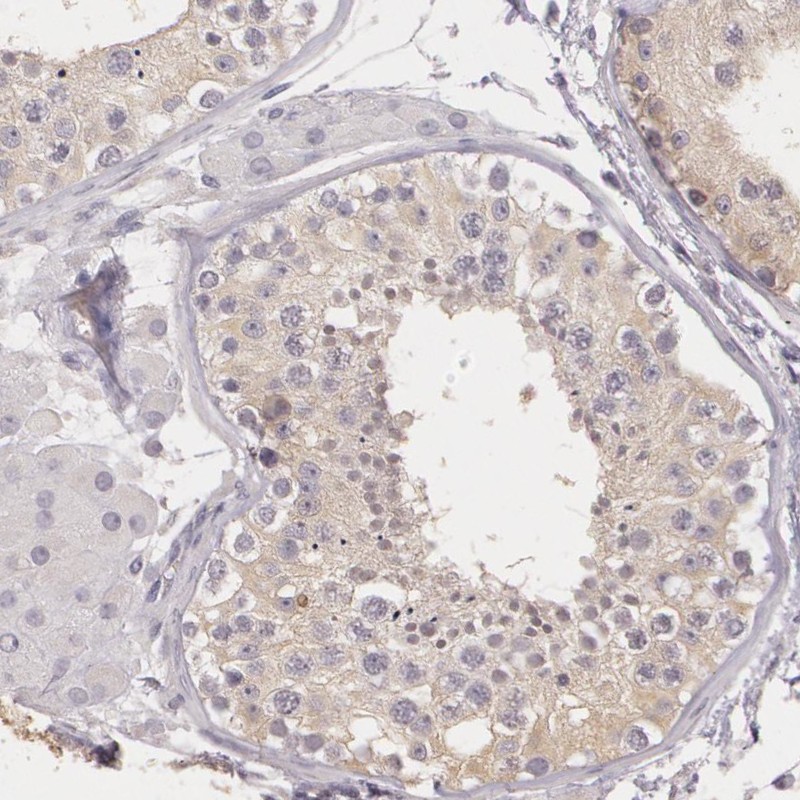

Immunohistochemical staining of human testis shows weak cytoplasmic positivity in cells in seminiferus ducts.